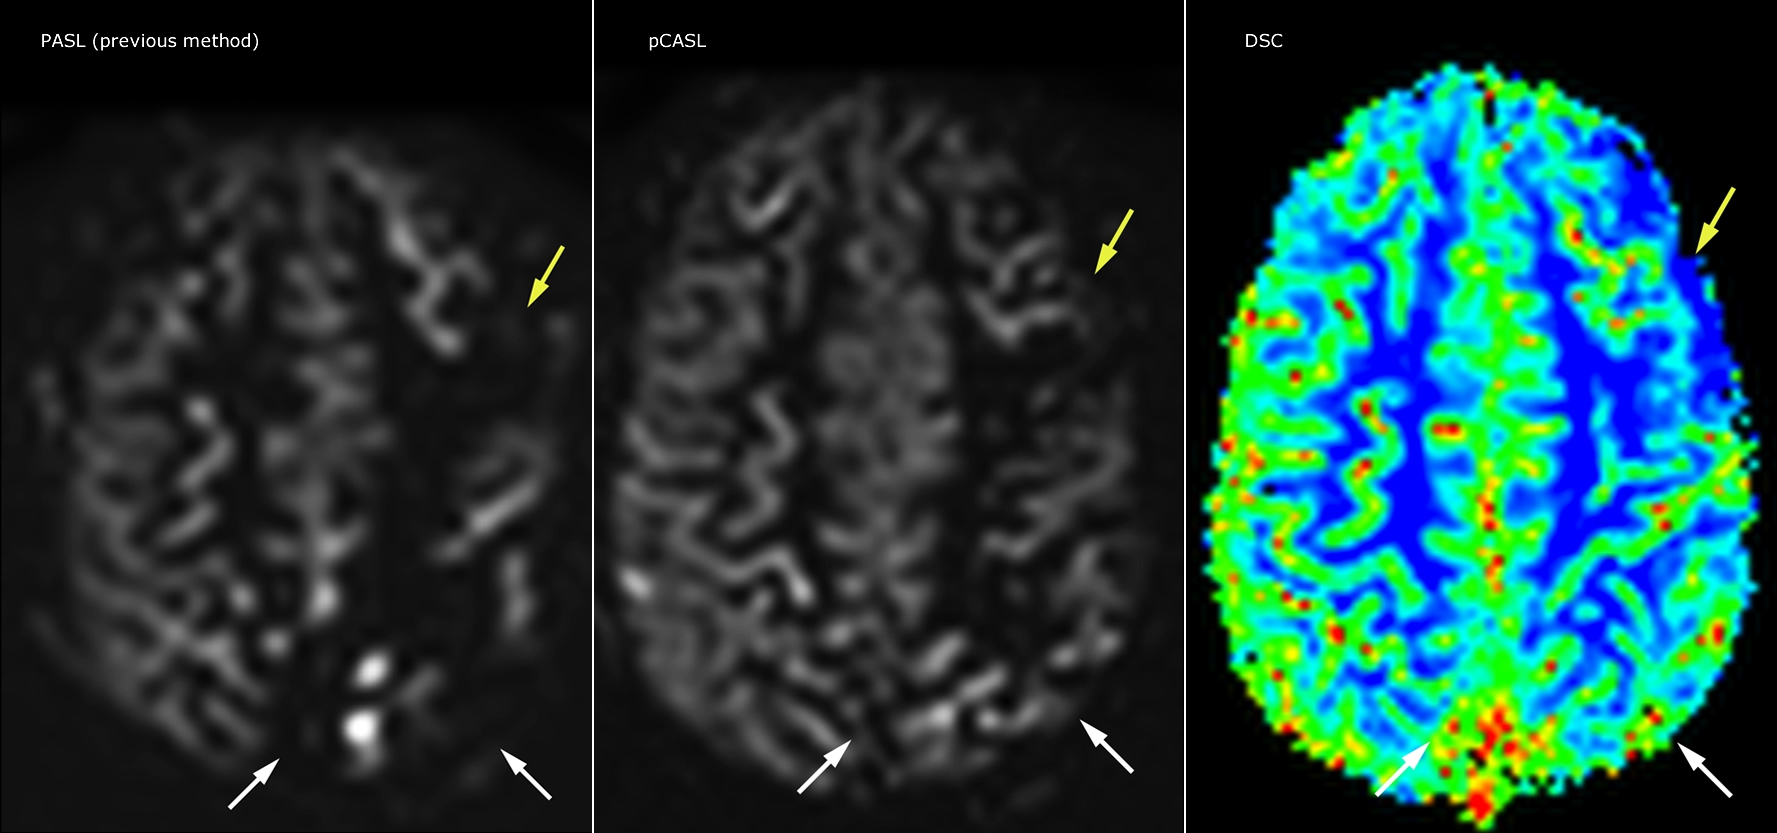

Pseudo-continuous arterial spin labeling (pCASL) was developed for brain perfusion imaging without contrast agent. “This is very desirable in pediatric patients where the general trend is to limit the administration of contrast,” says Dr. Miller. Growing confidence in specific applications “We built up confidence in pCASL by comparing it to contrast-based perfusion imaging. Once we had confidence that it was representing what the contrast perfusions were representing, we increased our diagnostic confidence by serial imaging in either the acute stage or the long term stages in a number of patients with arterial abnormalities.

Dr. Miller uses pCASL for all patients who present with chronic and acute cerebrovascular abnormalities such as acute stroke, as well as patients who present with signs of acute inflammation in the brain, and occasionally in patients with tumors, to assess the perfusion status of their tumor.

“In combination with diffusion weighted imaging, it can help give a more extended assessment of the degree of perfusion abnormality in a patient who is suffering acute ischemia. We have a number of patients who have chronic arterial insufficiency due to prior arterial abnormalities or acquired arterial abnormalities such as sickle cell disease or neurofibromatosis. Sometimes the child’s first manifestation of disease progression is a reduction in brain perfusion before stroke symptoms manifest clinically or in diffusion weighted imaging. We use pCASL to help delineate the perfusion abnormality.”

To other new users I would recommend to also start to interpret the pCASL images in comparison with other standard imaging – T2 and FLAIR and DWI – until the user gains confidence in interpreting these images by themselves.” “A powerful use of pCASL is in patients with chronic cerebrovascular stenosis, where clinicians desire information on how compensatory mechanisms of the brain are performing to enable perfusion to the brain. Often clinicians take into account how the compensatory mechanisms appear to help to provide adequate perfusion to the patient’s brain, and they may intervene surgically or make some other management decision.” “Another special application is the assessment of cerebrovascular reactivity with a Diamox perfusion exam, where we subtract two sets of pCASL images.”

“pCASL has now become more of a first-line scan for assessing perfusion for us, as opposed to DSC-based perfusion imaging with contrast agent. And in patients who were not planned to have contrast, we can perform pCASL for perfusion imaging without need to stop the exam, pull the patient out, and put in an IV. It also negates the postprocessing that’s necessary for dynamic susceptibility contrasts. And it allows us to repeat perfusion imaging in the same patient at the same imaging time, which is helpful in terms of patient motion, or in a situation where a scan needs to be done before pharmacological perfusion imaging.”